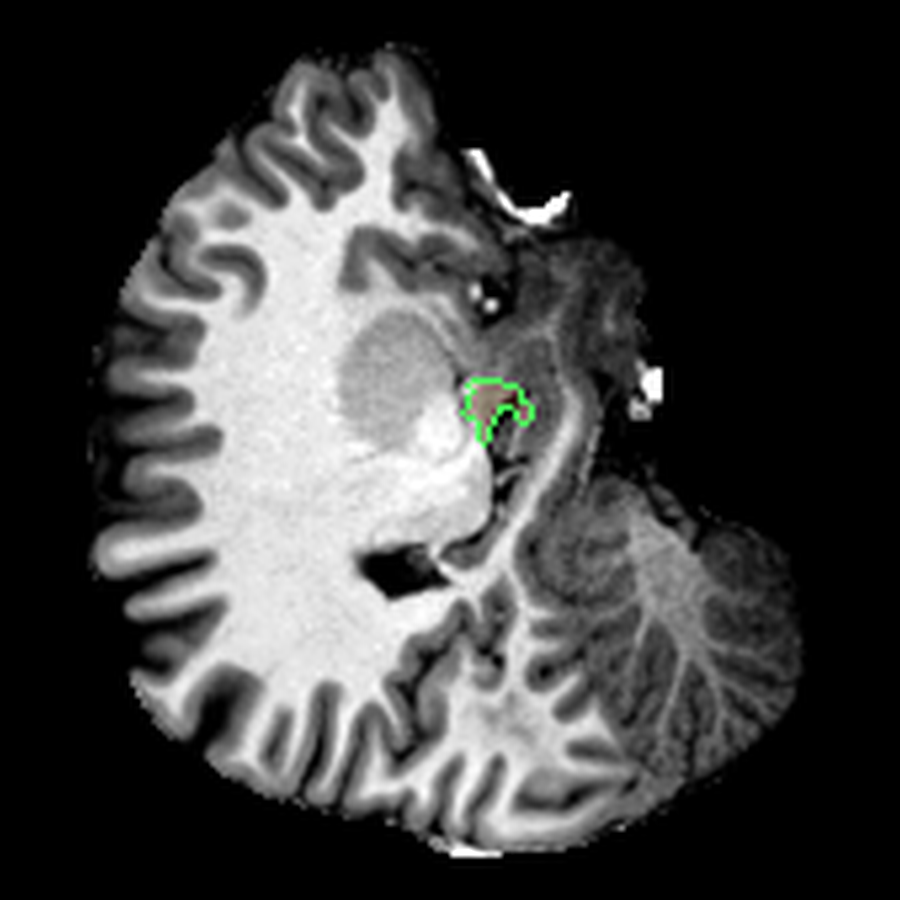

After the four-hour analysis, FreeSurfer had already given me what I needed to inspect the scan: a segmented volume that could be overlaid directly on the anatomical MRI. Visualising that (using a tool like ITK-SNAP), I got something a bit more interpretable than the original slices:

These are three orthogonal slices of my brain, with borders drawn around FreeSurfer’s own segmentations.

What I liked about having this data was that it changed how I interacted with the scan. Instead of staring at individual slices and guessing at the composition, I could start isolating specific parts of the brain.

The visualisations above show how little differentiation some brain regions have from their surroundings - I knew roughly where the thalamus was in the brain, but would never have been able to point it out on the MRI. At this stage, FreeSurfer plus some code had given me a perspective that would have been impossible for me to achieve myself.